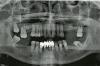

Необходима небольшая консультация по плану лечения.

Вверху предлагается удалить 3 крайних зуба слева/справа,

они подвижны. Оставшиеся шинировать. И съемный протез

Теперь вопрос, действительно ли надо депульпировать ВСЕ верхние зубы?

Внизу мост удаляется, зубы под ним полностью оголилить, и то же протез. Съемный.